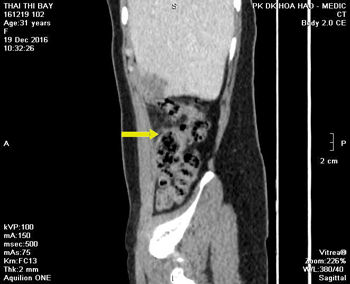

-Siêu âm doppler bụng cho thấy vùng gan (P) có hình ảnh ổ áp-xe cấu trúc echo hỗn hợp, đường kính d = 5,5cm, bờ nham nhở, kèm phù nề chủ mô gan xung quanh và tăng tưới máu nhẹ. Ngoài ra, đại tràng góc gan có hình ảnh dày vách, echo kém, d = 15mm, không hẹp lòng (Hình 1).

Hình 1. Khối áp-xe gan (P) và hình ảnh dày vách đại tràng góc gan trên siêu âm.